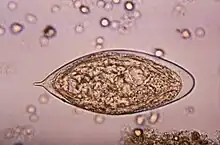

| Schistosoma mansoni egg | |

Thirteen species are found in Africa. Twelve of these are divided into two groups—those with a lateral spine on the egg (mansoni group) and those with a terminal spine (haematobium group).

Comparison of eggs